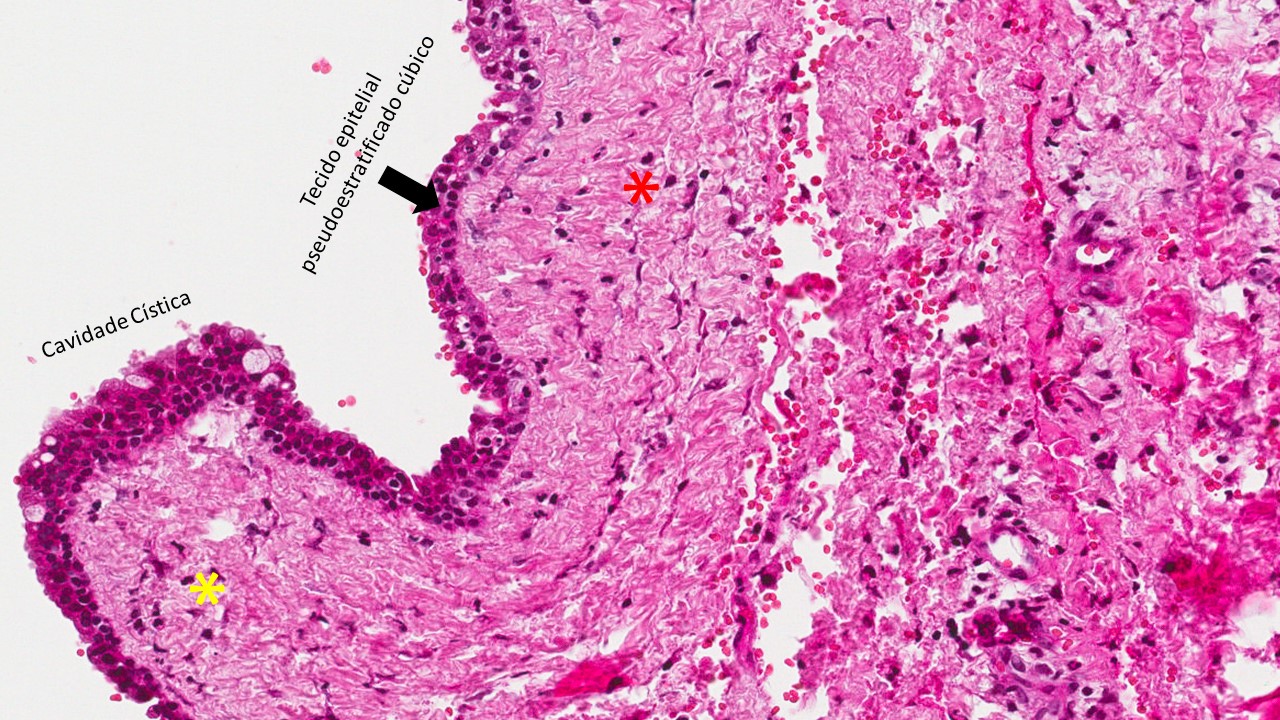

Descrição microscópica:

Observa-se cavidade (lúmen cístico) revestido por epitélio com caraterísticas variadas sendo em áreas estratificado, em outras simples, pseudoestratificado ou mesmo ciliado. A cápsula, constituída por tecido conjuntivo fibroso denso, pode apresentar infiltrado inflamatório linfoplasmocitário e em área focal nota-se o feixe vásculo-nervoso (origem do canal incisivo).

Dados importantes para o diagnóstico:

- Cavidade cística;

- Tecido epitelial pode ser de vários tipos, desde pavimentoso estratificado, simples, pseudoestratificado, ciliado, colunar ou cúbico simples;

- Tecido conjuntivo fibroso denso (asterisco amarelo);

- Infiltrado linfoplasmocitário (asterisco vermelho) na cápsula fibrosa;

- Feixe vásculo- nervoso (tracejado preto).

Cisto não-odontogênico que se origina a partir de remanescentes do epitélio do ducto lacrimal. Cisto que ocorre em tecido mole (não intraósseo).

O cisto nasolabial é revestido por epitélio colunar pseudoestratificado, exibindo muitas vezes células caliciformes e ciliadas, em áreas observa-se tecido epitelial com poucas camadas cuboidais. A cápsula exibe tecido conjuntivo fibroso denso (asterisco vermelho) com vasos sanguíneos, infiltrado inflamatório crônico (asterisco amarelo), e tecido muscular estriado esquelético subjacente.

Dados importantes para diagnóstico:

- Tecido epitelial que pode ser variado (estratificado com poucas camadas, pseudoestratificado ciliado);

- Cápsula de tecido conjuntivo fibroso denso;

- Infiltrado inflamatório linfoplasmocitário.